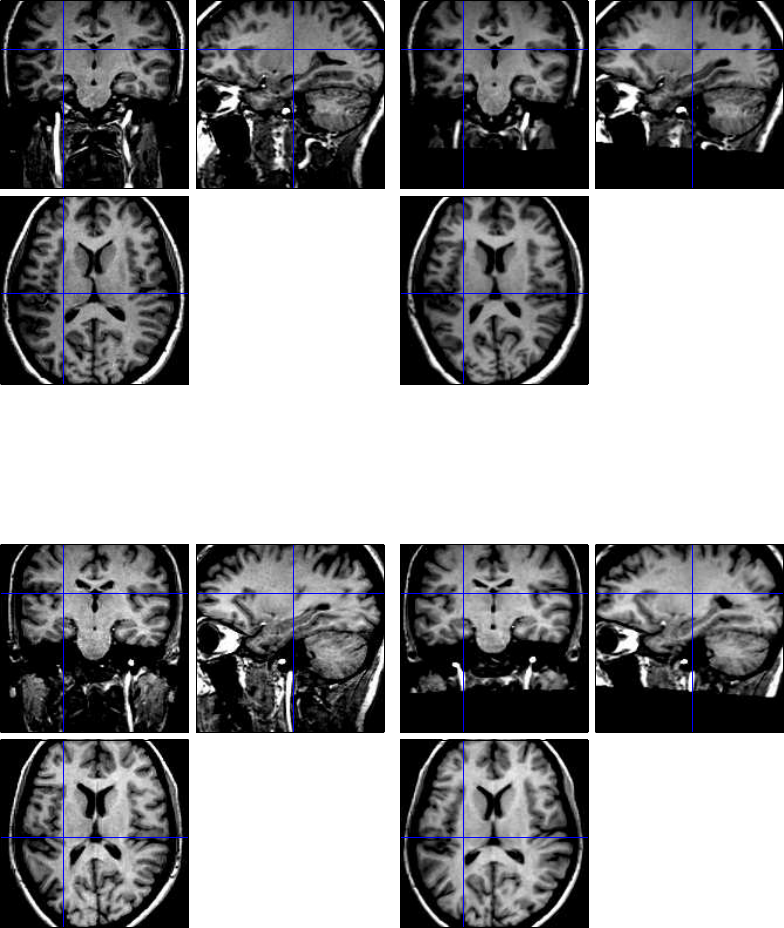

31.1 Spatial pre-processing ..................................243

31.1.1 Display ......................................243

31.1.2 Realignment ...................................243

31.1.3 Slice timing correction ..............................248

31.1.4 Coregistration ..................................248

31.1.5 Segmentation ...................................248

31.1.6 Normalise .....................................251

31.1.7 Smoothing ....................................251